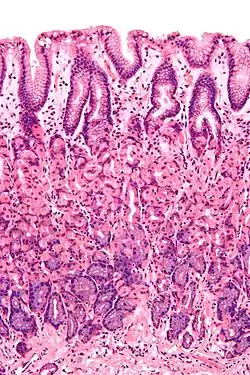

The epithelium, the most exposed part of the mucosa, is a glandular epithelium with many goblet cells. Goblet cells secrete mucus, which lubricates the passage of food along and protects the intestinal wall from digestive enzymes. In the small intestine, villi are folds of the mucosa that increase the surface area of the intestine. The villi contain a lacteal, a vessel connected to the lymph system that aids in the removal of lipids and tissue fluids. Microvilli are present on the epithelium of a villus and further increase the surface area over which absorption can take place. Numerous intestinal glands as pocket-like invaginations are present in the underlying tissue. In the large intestines, villi are absent and a flat surface with thousands of glands is observed. Underlying the epithelium is the lamina propria, which contains myofibroblasts, blood vessels, nerves, and several different immune cells, and the muscularis mucosa which is a layer of smooth muscle that aids in the action of continued peristalsis and catastalsis along the gut.

The wall of the stomach. Cross-section histology of intestinal villi of the human terminal ileum.

Cross-section histology of intestinal villi of the human terminal ileum.